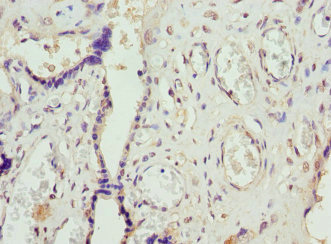

图片:

产品描述:FCGRT polyclonal antibody CSB-PA008545EA01HU was produced in the rabbits immunized by using the Recombinant Human IgG receptor FcRn large subunit p51 protein (24-297AA) as the immunogen. The target protein FCGRT is a cell surface receptor that binds the Fc region of monomeric immunoglobulin G. This protein transfers immunoglobulin G antibodies from mother to the newborn across the placenta. Besides, it also binds immunoglobulin G to protect the antibody from degradation. Diseases associated with FCGRT include selective Igg deficiency disease and immunodeficiency.

This Rabbit anti-Homo sapiens (Human) FCGRT Polyclonal antibody was tested in the ELISA, WB, IHC and IF applications. The non-conjugated IgG got purified by protein G and reached up to 95% in purity. It reacts with the FCGRT proteins of human or mouse-origin and may be used to detect the endogenous levels of FCGRT protein. -

应用范围:ELISA, WB, IHC, IF

Application Recommended Dilution WB 1:500-1:2000 IHC 1:20-1:1000 IF 1:50-1:200 -